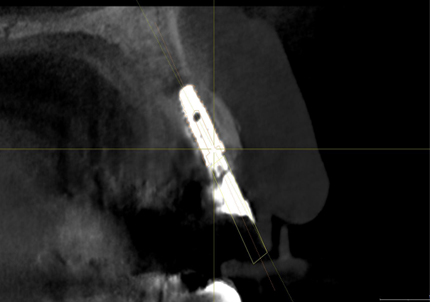

← 右上1番 SST CT画像

※ CT画像にて歯根片が確認できる

← 左上2番 SST CT画像

← 右上2番 通常の埋入 CT画像